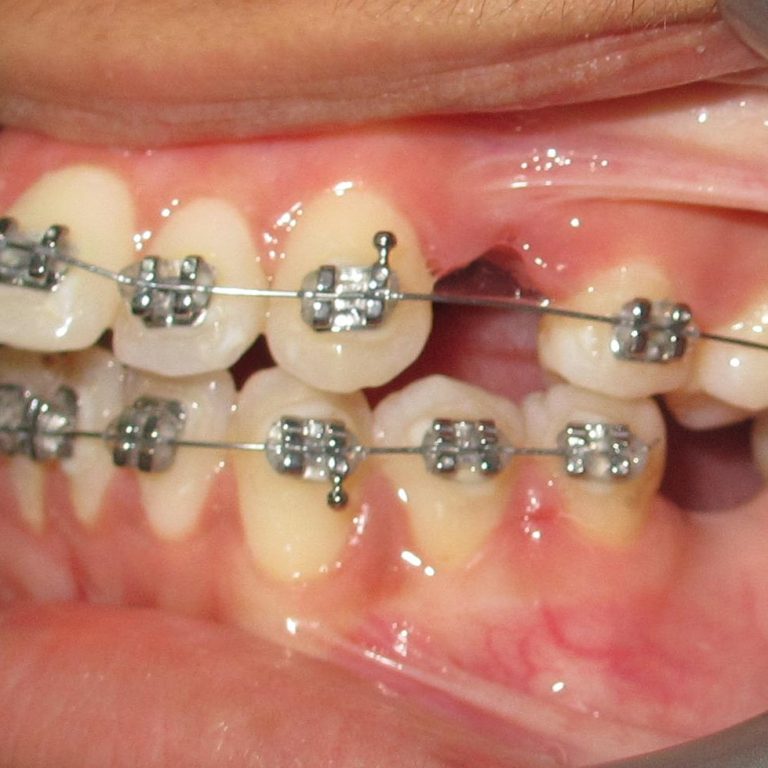

In today’s world of modern dentistry, patients seeking orthodontic treatment are often presented with two main options: traditional …